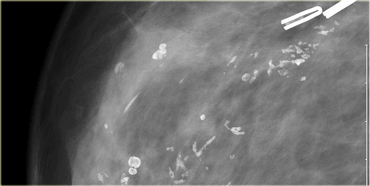

Click to enlarge Click to enlarge

Here another example of the tatoo-sign.

First notice that there are some calcifications that are clearly located within the skin (arrows).

The cluster calcifications on the MLO-view has the exact configuration as the cluster on the CC-view (next image).

On the CC-view the configuration of the microcalcifications is exactly the same.

If these calcifications were located in the centre of the breast they should have a different configuration, because the projection is different.

Only when calcifications are located within the skin their configuration stays the same.